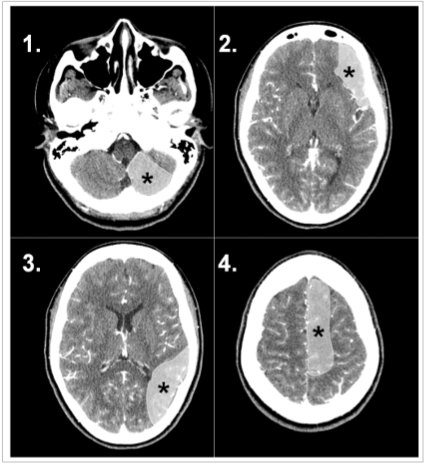

A doença vascular encefálica isquêmica pode determinar diferentes síndromes clínicas a depender do território arterial acometido. A percepção destas síndromes clínicas informadas no pedido médico pode auxiliar o radiologista na percepção de sinais precoces de isquemia intracraniana.

Com base na análise das imagens apresentadas, o território arterial acometido e as respectivas síndromes clínicas proporcionadas são, respectivamente: